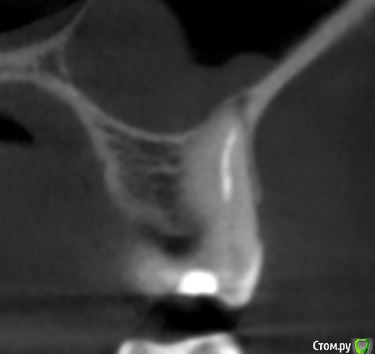

dmitrib81 Опубликовано 19 февраля, 2020 Поделиться Опубликовано 19 февраля, 2020 Помогите определить источник боли в зубе Ссылка на комментарий

krokomot Опубликовано 19 февраля, 2020 Поделиться Опубликовано 19 февраля, 2020 в медиальном корне недопломбировка и наличие вероятно 4ого канала. Ссылка на комментарий

dmitrib81 Опубликовано 20 февраля, 2020 Автор Поделиться Опубликовано 20 февраля, 2020 Зуб делали много лет назад. Примерно неделю назад появились периодические боли, бывает целый день не болит, потом снова ноющая боль. С приёмом пищи никак не связано. На горячие и холод реакции нетПодскажите, может ещё прислать фоток из КТ Пикассо, а то я в этом ничего не понимаю, просто разных фото экрана прислал, без какого-либо понимания, на что смотреть.. Ссылка на комментарий